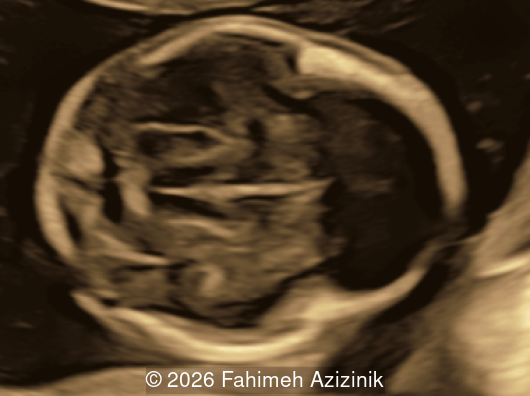

Image 4

• Bicoronal craniosynostosis

• Hypertelorism

Craniosynostosis is defined as the premature fusion of one or more cranial sutures, which leads to secondary distortion of skull shape due to restricted growth perpendicular to the fused suture and compensatory overgrowth at the non-fused sutures [3,4]. Single‑sutural craniosynostosis is typically an isolated, non‑syndromic finding. Nevertheless, a subset of cases, particularly those involving the coronal sutures, may have an underlying genetic etiology. Conversely, in syndromic craniosynostosis mutations are common, most frequently involving the fibroblast growth factor receptor genes (FGFR2 and FGFR3), as well as TWIST1 and EFNB1 [5]. FGFR-related craniosynostosis syndromes are characterized by bicoronal craniosynostosis, distinctive facial features, and variable hand and foot findings. Prenatal diagnosis of isolated cases of craniosynostosis is infrequent as the characteristic findings on ultrasound, which include decreased hypoechoic space between the skull bones, altered cranial shape, abnormal cephalic index, and the "brain shadowing sign", are not evident during the routine mid-trimester scan [6,7]. These syndromes share characteristic craniofacial features, often referred to as a ‘Crouzenoid face’, including midfacial retrusion, hypertelorism, proptosis due to shallow orbits, a high‑arched palate, flattened malar region, and a beaked nose [3,8].

Bicoronal synostosis is the characteristic cranial hallmark of Apert syndrome, detectable sonographically from 18 weeks. Its most recognizable manifestation is turribrachycephaly, defined by an elevated cephalic index (typically >85–90%) and a tall cranial vault with marked frontal bossing [19]. On prenatal ultrasound, the face in Apert syndrome shows midface hypoplasia with a depressed nasal bridge, proptosis, hypertelorism, and frontal bossing. The extremities demonstrate syndactyly of both bone and soft tissue of the hands and feet with partial-to-complete fusion often involving second, third, and fourth digits, known as “mitten hands” and “socked feet”. In severe cases, all digits are fused, with the presence of a single nail known as “synonychia” [20]. Other ultrasound findings include mild ventriculomegaly, agenesis of the corpus callosum, deficient or absent septum pellucidum, and fusion of the cervical vertebrae at the level of C5-C6 [21]. Cardiovascular (atrial and ventricular septal defect) and genitourinary anomalies (hydronephrosis, and cryptorchidia) are present in 10% of patients [22]. Increased nuchal translucency in the first trimester [23], widely open metopic suture [24], and polyhydramnios [25] have also been reported. Three-dimensional (3D) ultrasound facilitates assessment of surface abnormalities of the face and extremities, and magnetic resonance imaging (MRI) can be used to evaluate associated intracranial conditions [26].